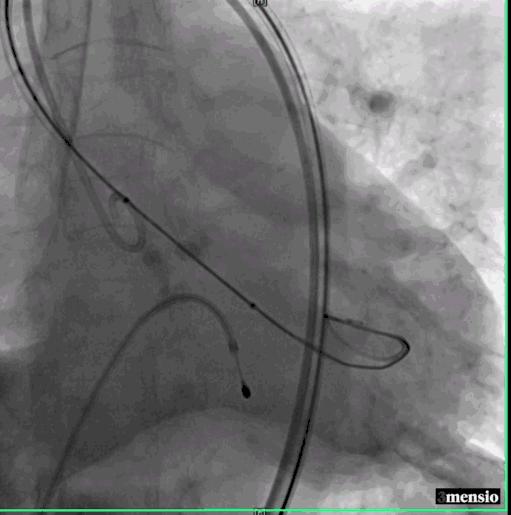

危险在此时发生了,球囊扩张后,患者出现血压下降,造影发现钙化的瓣膜扩开后出现大量反流,手术团队当即决定马上植入已经预装好的23号瓣膜,且因为预扩张球囊的反馈情况,把原有定额17ml减少2ml至15ml,成功跨瓣后精确定位并在临时起搏器180次/分起搏控制血压下于高位释放,过程顺利。

球囊扩张后重度返流

瓣膜定位

瓣膜释放